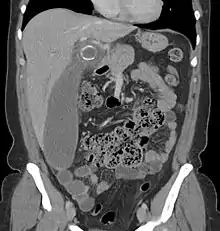

Computed tomography

Where it is readily available, computed tomography (CT) has become frequently used, especially in people whose diagnosis is not obvious on history and physical examination. Concerns about radiation tend to limit use of CT in pregnant women and children, especially with the increasingly widespread usage of MRI.[49][50]

The accurate diagnosis of appendicitis is multi-tiered, with the size of the appendix having the strongest positive predictive value, while indirect features can either increase or decrease sensitivity and specificity. A size of over 6 mm is both 95% sensitive and specific for appendicitis.[51]

However, because the appendix can be filled with fecal material, causing intraluminal distention, this criterion has shown limited utility in more recent meta-analyses.[52] This is as opposed to ultrasound, in which the wall of the appendix can be more easily distinguished from intraluminal feces. In such scenarios, ancillary features such as increased wall enhancement as compared to adjacent bowel and inflammation of the surrounding fat, or fat stranding, can be supportive of the diagnosis. However, their absence does not preclude it. In severe cases with perforation, an adjacent phlegmon or abscess can be seen. Dense fluid layering in the pelvis can also result, related to either pus or enteric spillage. When patients are thin or younger, the relative absence of fat can make the appendix and surrounding fat stranding difficult to see.[52]